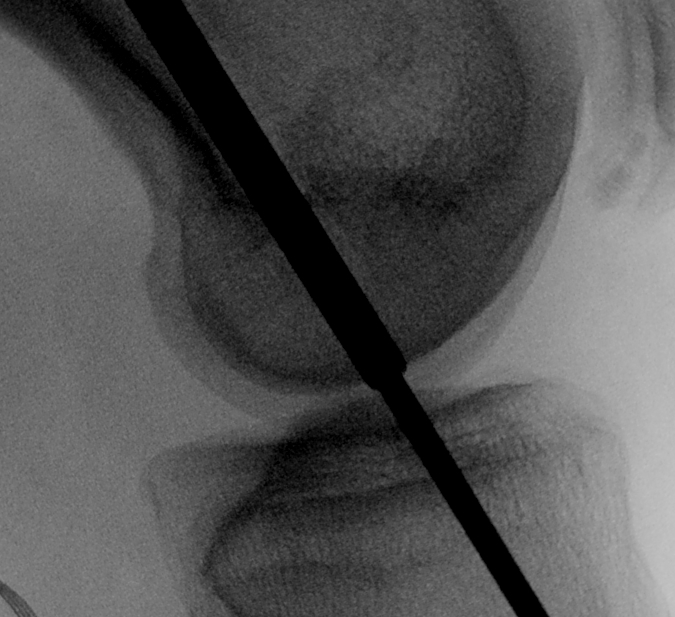

Pass graft

- measure tibial tunnel

- apply artery forcep at appropriate distance from central graft

- allows you to know when graft is pulled through enough

- the LARS has a specifice portion designed to be inside the native ACL

- pass from the tibia up through the knee into the femur

Secure

- insert femoral screw outside in

- tension tibial side

- must not overtension as there is no give in the graft

- secure tibial side with screw